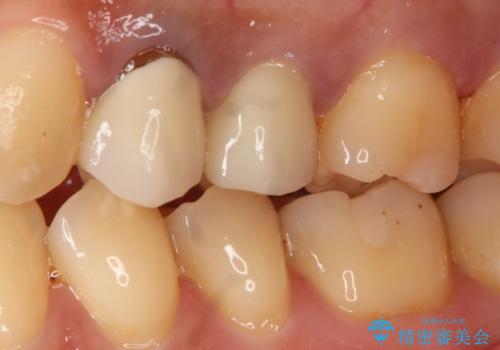

う蝕除去中に露髄 フルジルコニアクラウン

- 99000円(フルジルコニアクラウン+仮歯)費用は治療当時の料金となります

う蝕除去中に露髄したため精密根管治療へと切り替え、仮歯をはさんでセラミッククラウンを装着し終了としました。